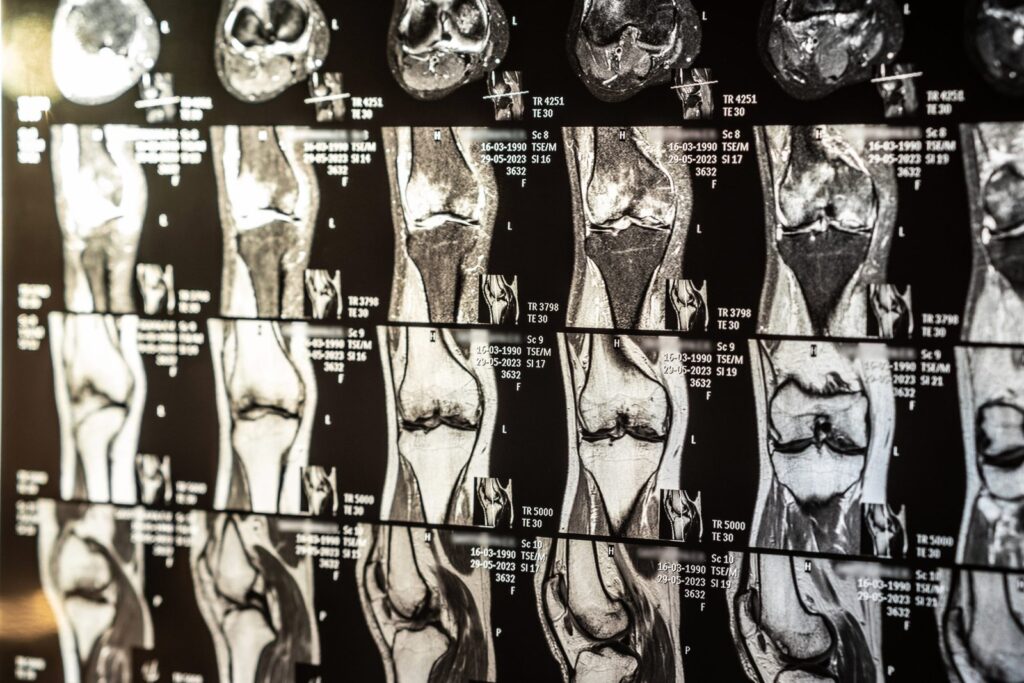

Antes de cirurgias ortopédicas, a ressonância magnética fornece imagens detalhadas das estruturas afetadas, permitindo que o médico escolha a melhor abordagem cirúrgica.

No pós-operatório, a ressonância magnética é utilizada para monitorar a recuperação, garantindo que o tratamento esteja evoluindo conforme o esperado.